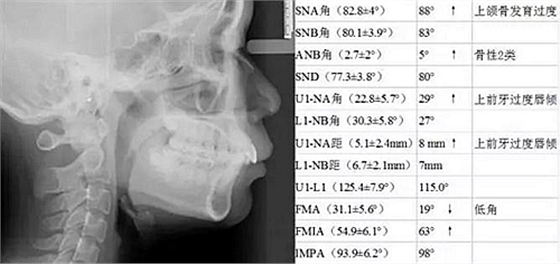

頭影測量對比

上牙列得到有效內(nèi)收,上前牙凸度亦得到改善。

頭影測量顯示為骨性Ⅱ類低角患者。